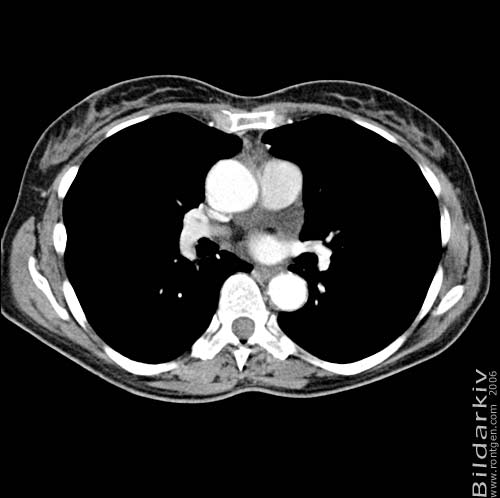

Snitt över thorax med kontrast. Sk. mediastinum-fönstersättning.

Mediastinum